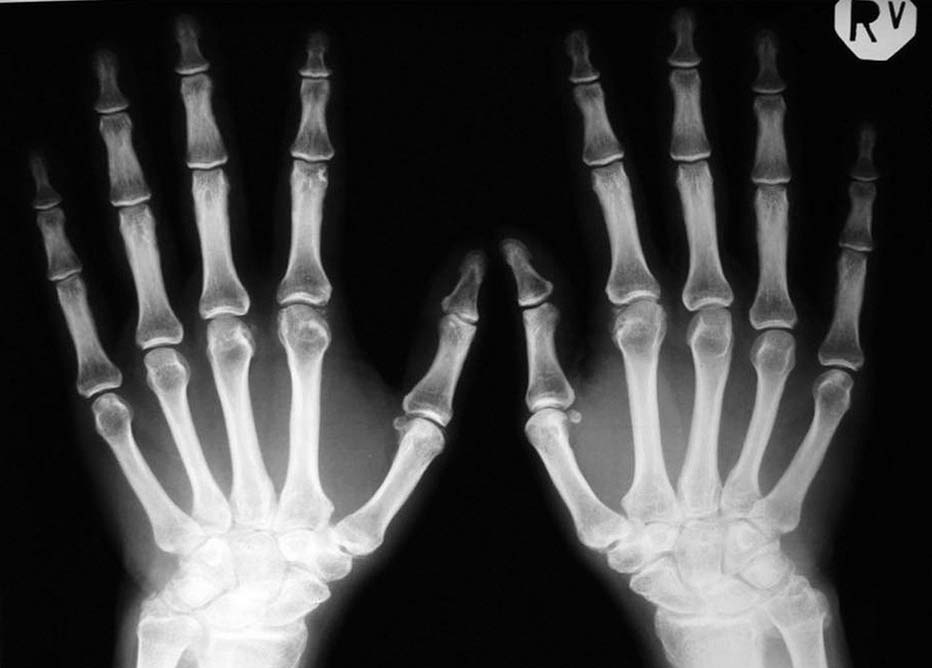

Cel: W pracy przedstawiono długoterminowe obserwacje słowackich pacjentów z chondrokalcynozą i nasilonymi zmianami w obrębie rąk w celu oszacowania, w jaki sposób zostaną oni zdefiniowani poprzez kryteria, wg których proponuje się klasyfikować pacjentów z zaburzeniami metabolizmu pirofosforanu wapnia.